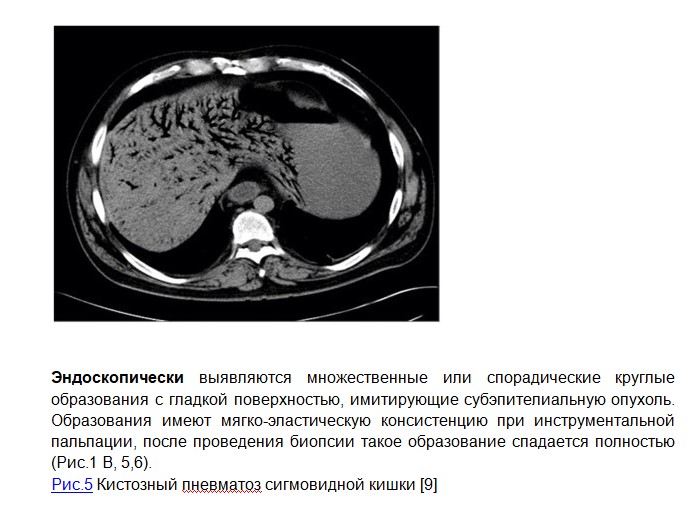

Диагностика. В целом, диагноз кистозного пневматоза кишечника основан на эндоскопии и рентгенологических методах (Рис.1), таких, как обзорная рентгенография и компьютерная томография органов брюшной полости, при этом компьютерная томография имеет большую чувствительность, в том числе для определения такого редкого и грозного проявления кистозного пневматоза, как образования газа в системе воротной вены (Рис. 3 E и F, 4), определение которого на обзорной рентгенограмме связано с высоким уровнем летальности (73-83%). Рентгенологические признаки газа в стенке кишечника могут быть разделены на кистозные и линейный. При кистозном пневматозе на фоне вздутия кишки определяются ячеистые структуры в виде виноградных скоплений или сотовидных теней вдоль стенки кишечника, обусловленные тесно расположенными кистозными образованиями разного размера и конфигурации (Рис. 1 А,D). [1,3] Линейный пневматоз характеризуется наличием полос, расположенных параллельно стенке кишки, циркулярным складкам или гаустрам. (Рис.2). Чаще линейный пневматоз связан с ишемией кишечника или инфарктом. Так же рентгенологические методы обследования позволяют выявить наличие свободного газа в брюшной полости. [5,8,10]

Кистозный пневматоз кишечника – редкое заболевание с невыясненной этиологией. Диагностика основана на сочетании эндоскопического и рентгенологических методов обследования. Эндоскопически заболевание проявляется множественными круглыми образованиями с гладкой поверхностью, имитирующими субэпителиальную опухоль. Рентгенологически выявляются скопления газа в толще стенки кишки на фоне ее вздутия. В большинстве случаев кистозный пневматоз кишечника проходит спонтанно, терапия направлена на лечение основного заболевания, на фоне которого развилось данное состояние, и только в некоторых случаях требуется экстренное хирургическое лечение.